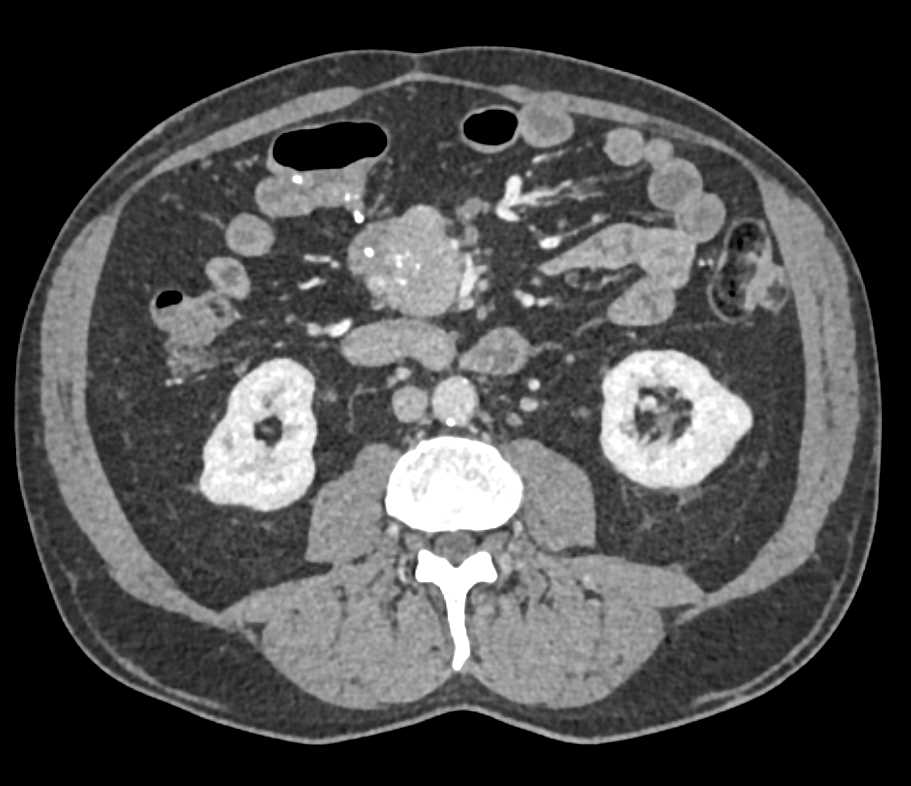

Carcinoid Tumor with Desmoplastic Reaction